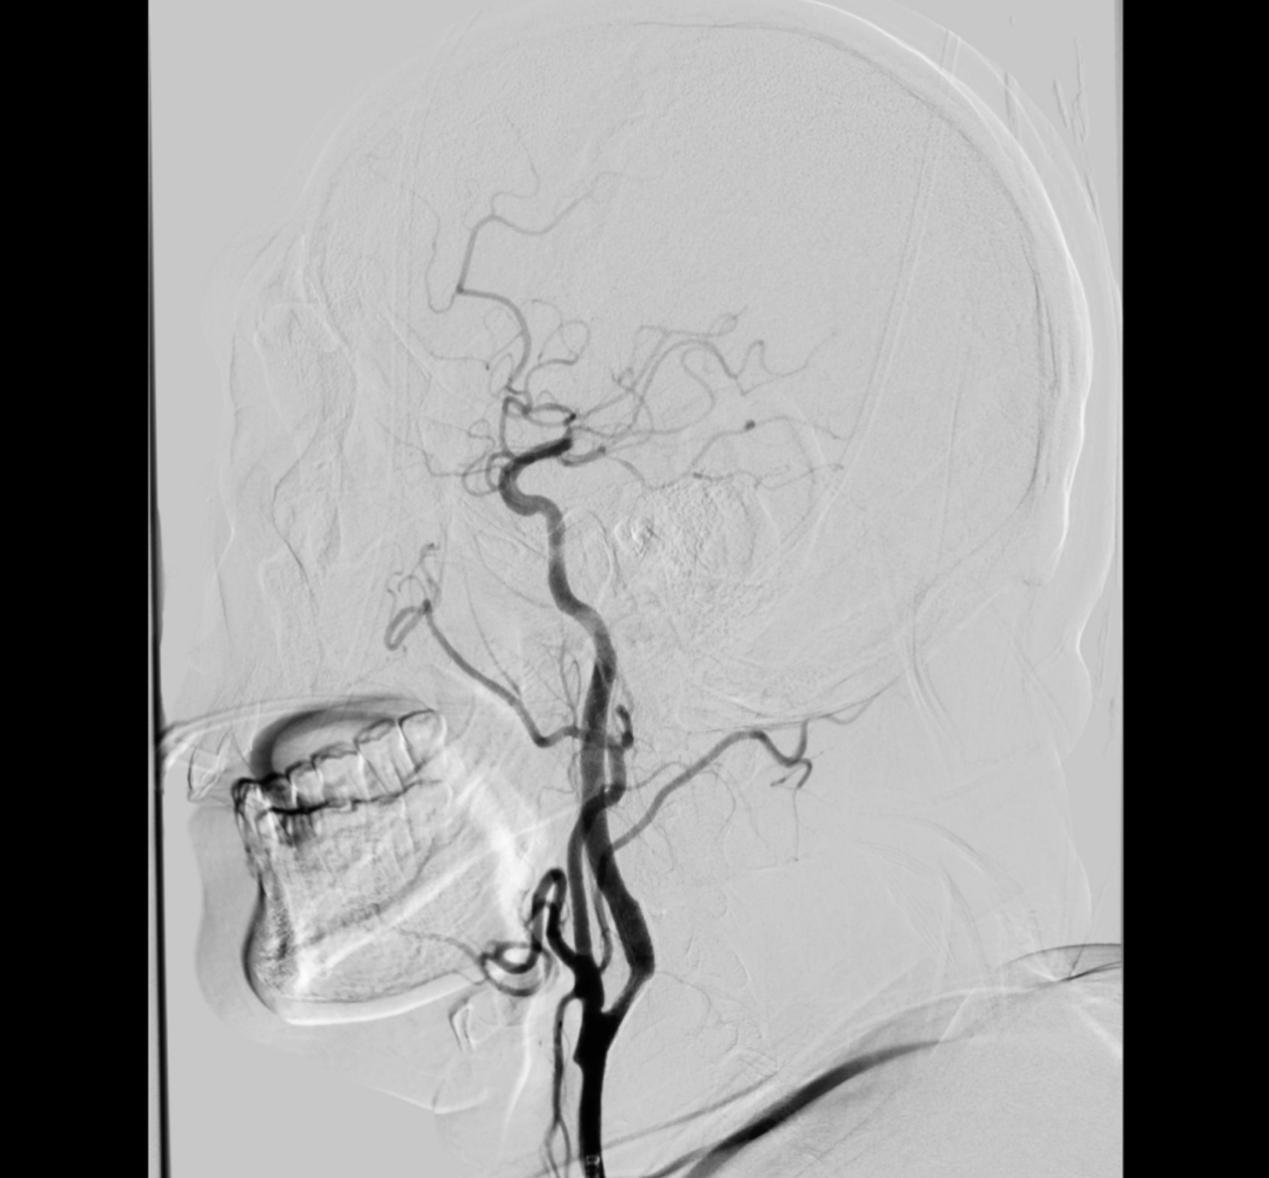

CTA提示右侧颈内动脉及大脑中动脉闭塞

右侧颈内动脉及大脑中动脉恢复通畅